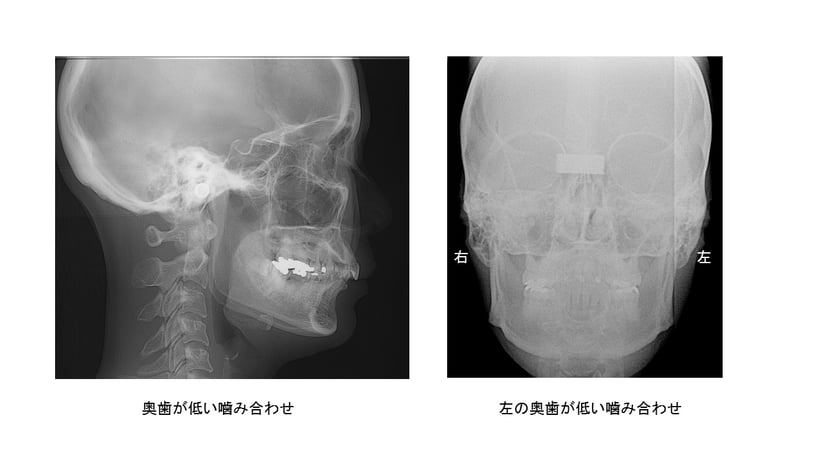

左は奥歯も前歯も低い噛み合わせ、右は左右で高さが違う噛み合わせです。